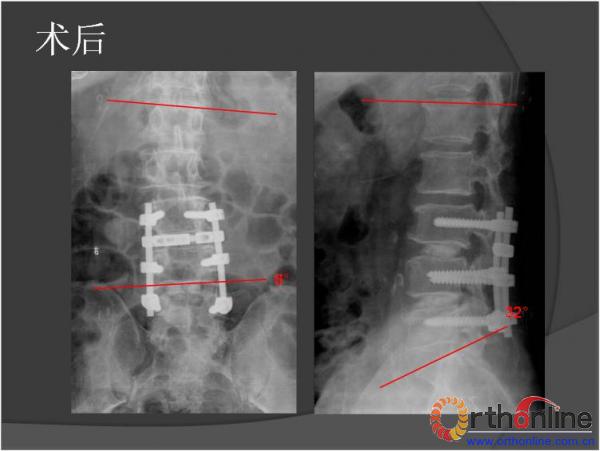

北京军区总医院骨科李放教授报告了一例腰椎管狭窄脊柱融合术后、退变侧凸加重并出现邻近节段退变病、而后进行翻修的病例。患者男性,64岁,2009年因腰椎管狭窄症行椎板减压,L3-4、L4-5PLIF手术,术后3年间疗效满意,后由轻度扭伤后再度出现腰痛及下肢疼痛,经检查后发现L2-3间盘退变、L1-2间盘突出并出现退变性腰椎侧凸,于2013年2月行翻修手术后痊愈。